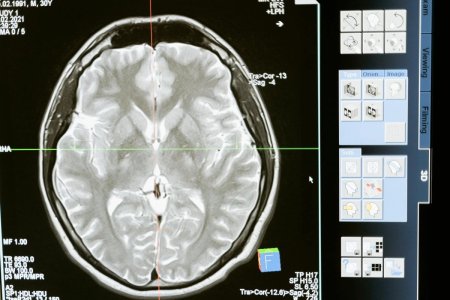

The brain plays a key role in balance and coordination—changes in these areas can sometimes signal underlying health issues. Image Source: Pexels / MART PRODUCTION.

The cerebellum, a small region near the base of the brain, helps control coordination and balance.

When something affects this area—such as a stroke, a neurological condition, or, in rare cases, a brain tumor—it can interfere with movements like the one in this test.